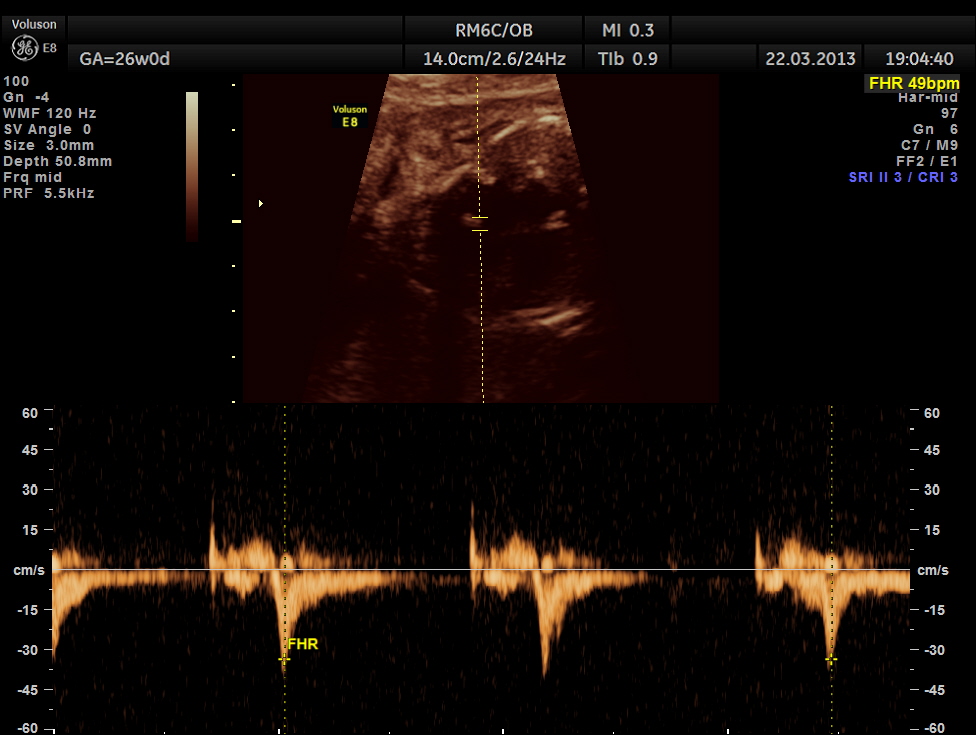

the following picture shows a probable transmitted rhythm with severe bradycardia